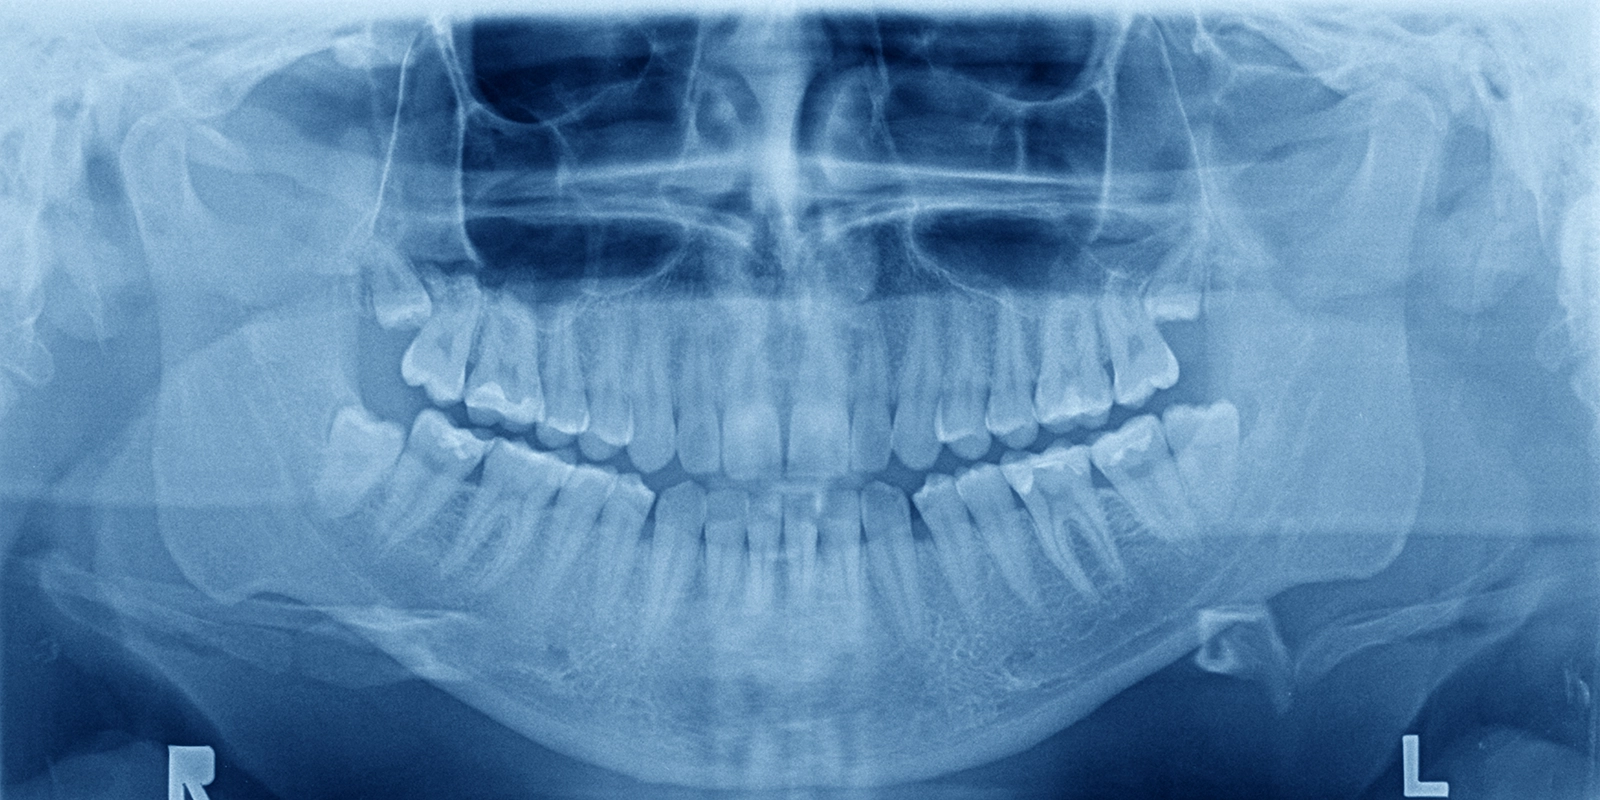

親知らずは、上下の顎の最も奥に生えてくる歯で、正式には「第三大臼歯」といい、一般的に10代後半から20代前半にかけて生えてくるため、親が知らないうちに生えることから「親知らず」と呼ばれるようになりました。

実は現代人の顎は昔の人と比べて小さくなってきているため、親知らずが生えるスペースが不足していることが多く、その結果として真っ直ぐ生えてこないケースが大半を占めているのです。横向きや斜めに傾いたまま歯茎の中に埋まっていたり、一部だけ顔を出していたりすることがよくあり、こうした生え方によってさまざまな問題を引き起こすことがあります。

CT検査による安全な抜歯

下顎の親知らずを抜歯する際には、神経の位置を正確に把握することが非常に重要になってきます。というのも下顎には「下歯槽神経」という太い神経が通っていて、この神経と親知らずの根が近接している場合があるからです。

当院ではCT検査を行って神経と親知らずの位置関係を三次元的に確認してから抜歯を行うようにしていて、これによって神経を傷つけるリスクを最小限に抑え、安全に抜歯することができるようになっています。